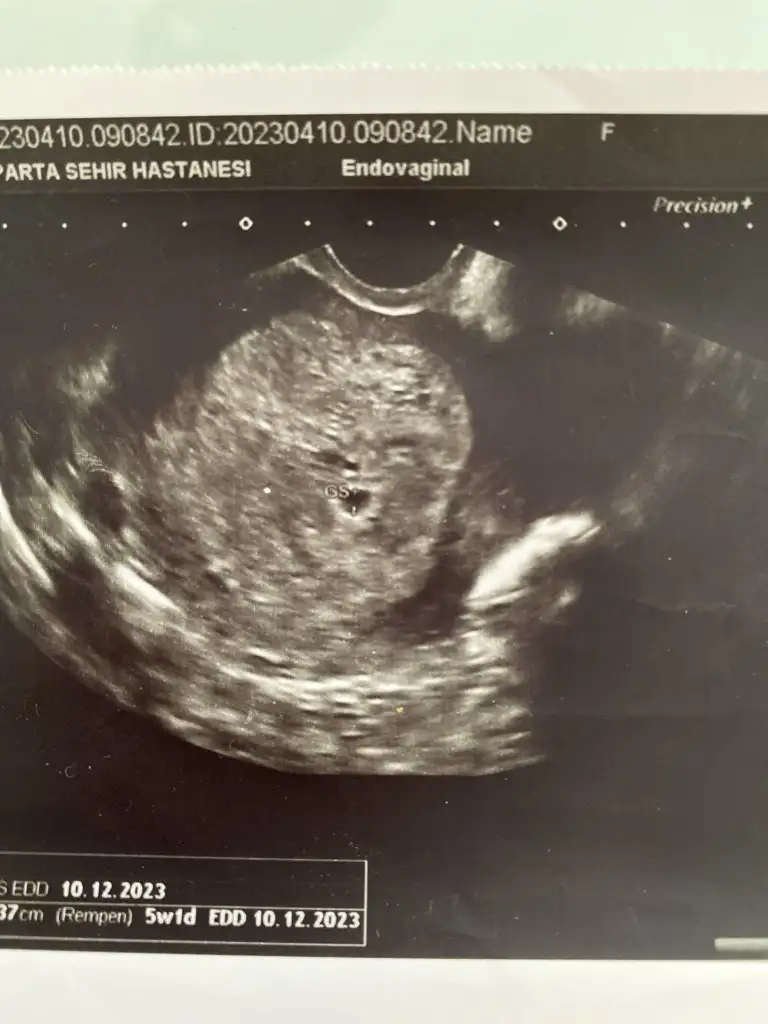

Herkese günaydın. Ben dün ikili test sonucumu almaya gittim, gitmişken de muayene olayım dedim bebek duruyor mu diye

doktor o sırada bir şeyle meşguldu, asistanı baktı, sekreteri de bilgisayardan asistana okudu riskleri. Yaş riski hariç düşük çıktı (yaş 1/59, down 1/1035 trisomi 18 13 1/300000 civarı). Güzel dediler (yaştan dolayı zaten fetal yaptıracağımı biliyorlardı) sonra sonucu istedim ama devlet hastanesi olduğu için yazıcıya gönderiyorlar, çıkarken alıyorsunuz bankodan. Alınca kan değerlerimin birinin yüksek olduğunu fark ettim. Serbest beta hcg 2.33 mom (papp-a mom 1.84) çıkmış ve doktorla konuşma şansım olmadı hiç (muayene sırasında riskler konuşuldu sadece kan değerlerini okumadı sekreter, gündeme gelmedi yani), bugün fetal için kan vereceğim ama geceden beri sözelci-dilci halimle tıp makalelerini tarıyorum (kimi 1.5 mom üstü kimi 2.5mom üstü yüksek kabul ediyor ve down olasılığına ek olarak preeklamsi, hipertansiyon vb gibi birçok gebelik komplikasyonuna işaret edebileceği söyleniyor, çoğu bulgu papp düşük bu yüksekse sorun diyor ama atipik bulgular da büyük bir oranı oluşturuyor vb.) şu aşamada burada böyle bir deneyimi olan yoktur muhtemelen ama yine de belki bir fikri olan vardır diye yazmak istedim. Bir de kombine risk, biyokimyasal risk vb hesaplanmamış hiç. Acaba riskleri hesaplarken kan değerlerini dahil etmediler mi demek oluyordur bu? Fetal için kan vereceğim bugün ama sonucu bekleyebilir miyim bilemedim.